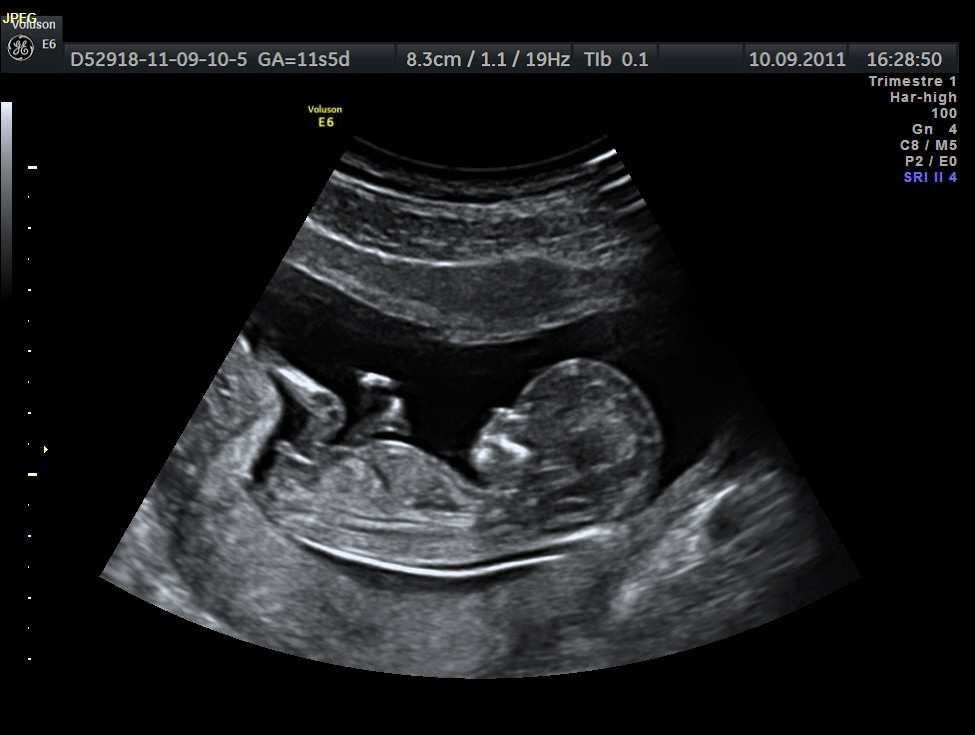

Another area of scientific focus involves prenatal environmental factors that may influence neurodevelopment. Researchers are examining how conditions during pregnancy—such as maternal health, nutrition, and exposure to certain environmental elements—may interact with genetic predispositions.

Studies suggest that prenatal environments play a role in shaping how the developing brain responds to growth signals. This does not imply direct causation, but rather a complex interaction between biological systems and environmental conditions. Factors such as inflammation, stress regulation, and metabolic balance during pregnancy are being explored for their potential influence on early brain organization.

One of the most consistently discussed areas in autism research focuses on timing during early brain development. Scientists suggest that autism may not arise from a single event, but rather from subtle changes occurring during critical windows of brain formation. During pregnancy and early infancy, the brain undergoes rapid growth, forming billions of neural connections that influence communication, sensory processing, and social behavior.

Research indicates that when this delicate timing is altered—due to genetic variations, biological signals, or environmental influences—the structure and function of neural networks may develop differently. This does not imply damage or deficiency, but rather variation in neurological wiring, which may contribute to traits associated with autism.

Scientists emphasize that these timing differences may affect how brain regions communicate with each other, potentially explaining differences in information processing, sensory sensitivity, or social interaction. Importantly, this research highlights autism as a developmental difference, not a disease or condition caused by a single harmful factor.

Understanding brain development timing helps researchers move away from oversimplified explanations and toward a more accurate, respectful understanding of neurodiversity. It reinforces the idea that autism is rooted in early development, long before behavioral traits become noticeable.